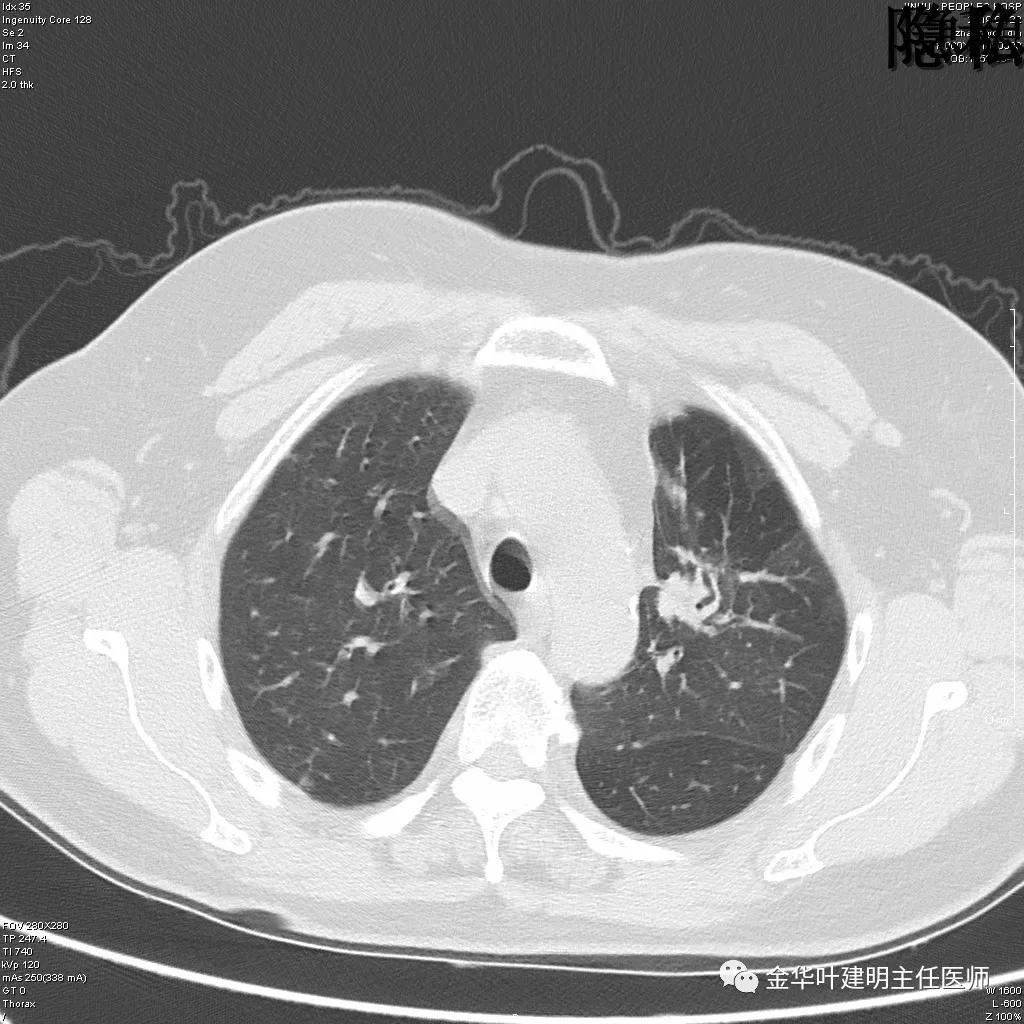

可见左肺下叶比较靠中央的部位也有一病灶,是混合磨玻璃影,偏实性,瘤肺边界清楚,是较为典型的肺癌表现。进一步的靶扫描图像如下:

靶扫描更清晰的显示细节,从影像上看,基本可以断定左下肺的是恶性肿瘤了,而且已经密度较高,长径也在3厘米以上,不能继续观察等待了!